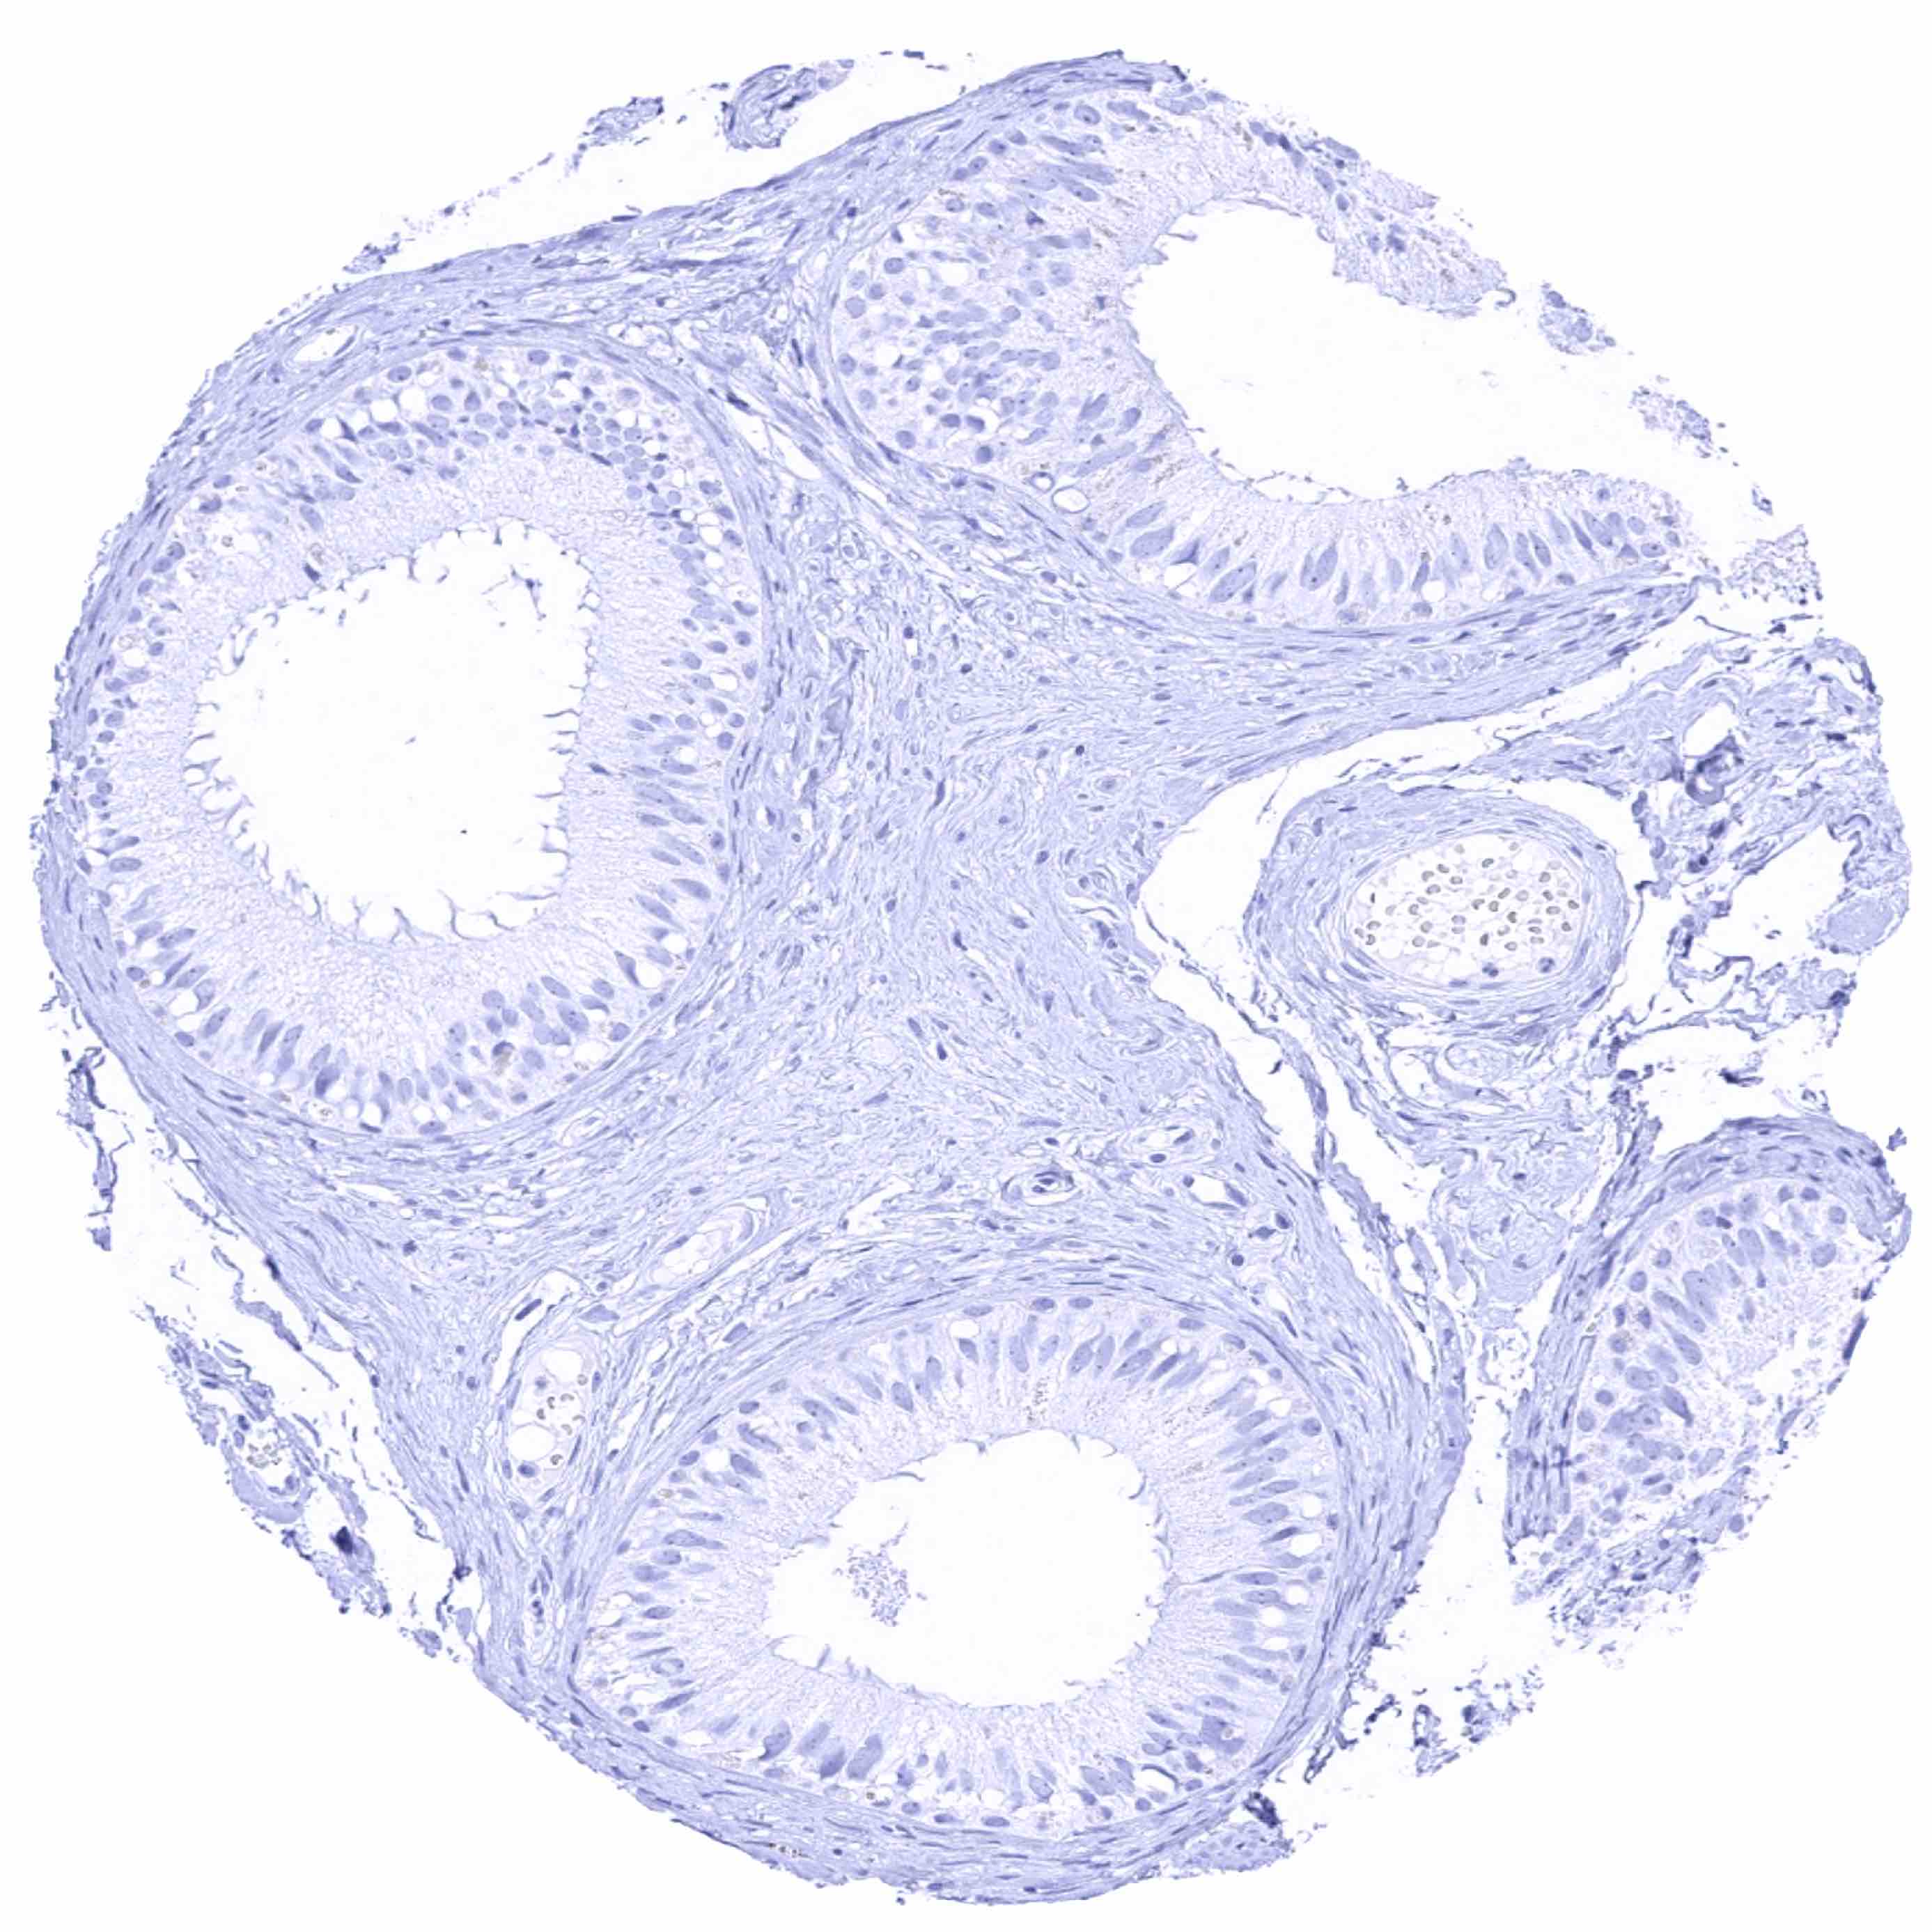

Epididymis (Caput)

Epididymis (Cauda)